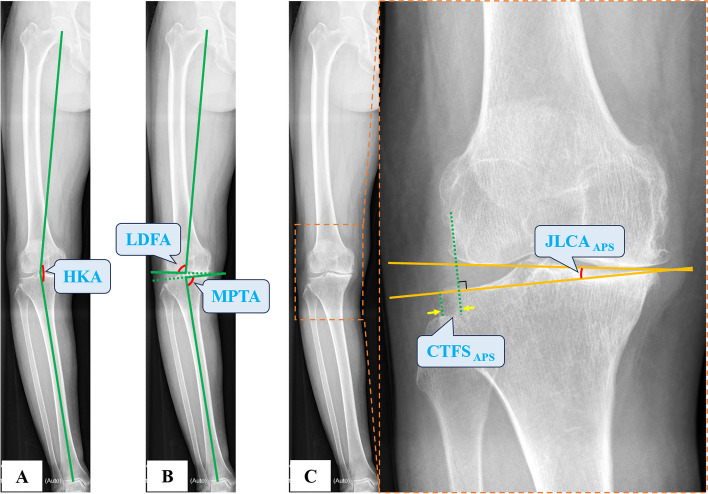

Methods: We analyzed 306 knees retrospectively using preoperative hip-to-ankle anteroposterior standing (APS) radiographs, anteroposterior (AP) and lateral knee radiographs, AP valgus stress (VS) force radiographs, and standard orthogonal MRI. Based on the intraoperative visualization, the knees were grouped into ACL functionally-intact and ACL functionally-deficient (ACLD) groups. The diagnostic validity and reliability were calculated based on the radiograph parameters such as hip-knee-ankle angle (HKA), medial proximal tibial angle (MPTA), lateral distal femoral angle (LDFA), posterior tibial slope (PTS), sagittal tibiofemoral subluxation (STFS), coronal tibiofemoral subluxation (CTFS), joint line convergence angle (JLCA), the maximum wear point of the proximal tibia plateau (MWPPT%), and MRI parameters including ACL grades and MWPPT%.